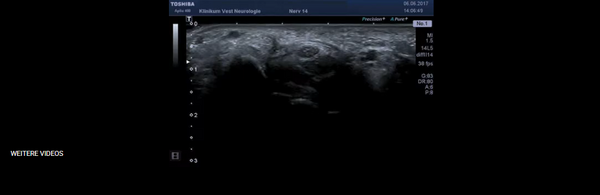

Ultraschall der Nerven und Muskeln

Durch moderne hochauflösende Ultraschallgeräte können heute auch Nerven und Muskeln an Rumpf und Extremitäten sehr gut untersucht werden. Besondere Bedeutung hat diese Methode bei Patienten mit sogenannten Nerven-Engpass-Syndromen (am häufigsten Karpaltunnelsyndrom und Ulnaris-Neuropathie am Ellenbogen). Auch für die Diagnostik von erblichen oder immun-vermittelten Polyneuropathien und Muskelkrankheiten spielt der Ultraschall eine zunehmend wichtige Rolle.